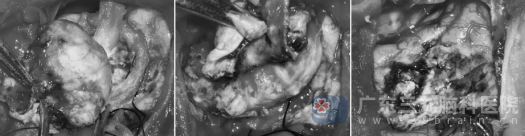

经过周密的术前准备,由科室专家主刀,在全麻下为王阿婆实施了开颅肿瘤切除术。手术历时5个小时,术中可见病变血供异常丰富,与术前影像学判断完全吻合。凭借精湛的显微神经外科手术技巧,医生在充分保护正常脑组织及重要功能区的前提下,将肿瘤完整切除。术后MR复查显示:病变已完全切除。